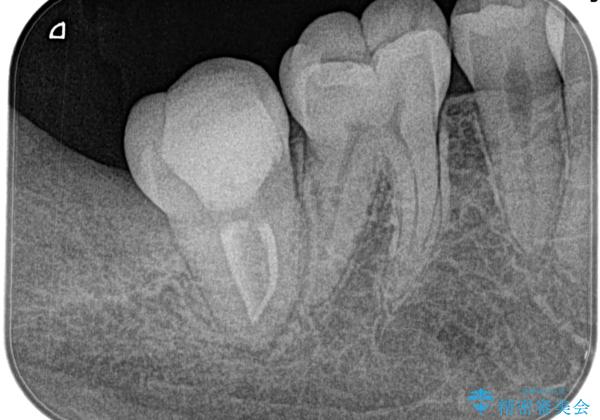

【根管治療】ズキズキ痛い歯

- 3日前からズキズキ痛み、冷たいものや熱いもので持続痛もあるとのこと。

不可逆性歯髄炎の診断で抜髄処置を行なっています。

- 精密根管治療(イニシャルケース,大臼歯):122,000円、ファイバーコア:22,000円費用は治療当時の料金となります